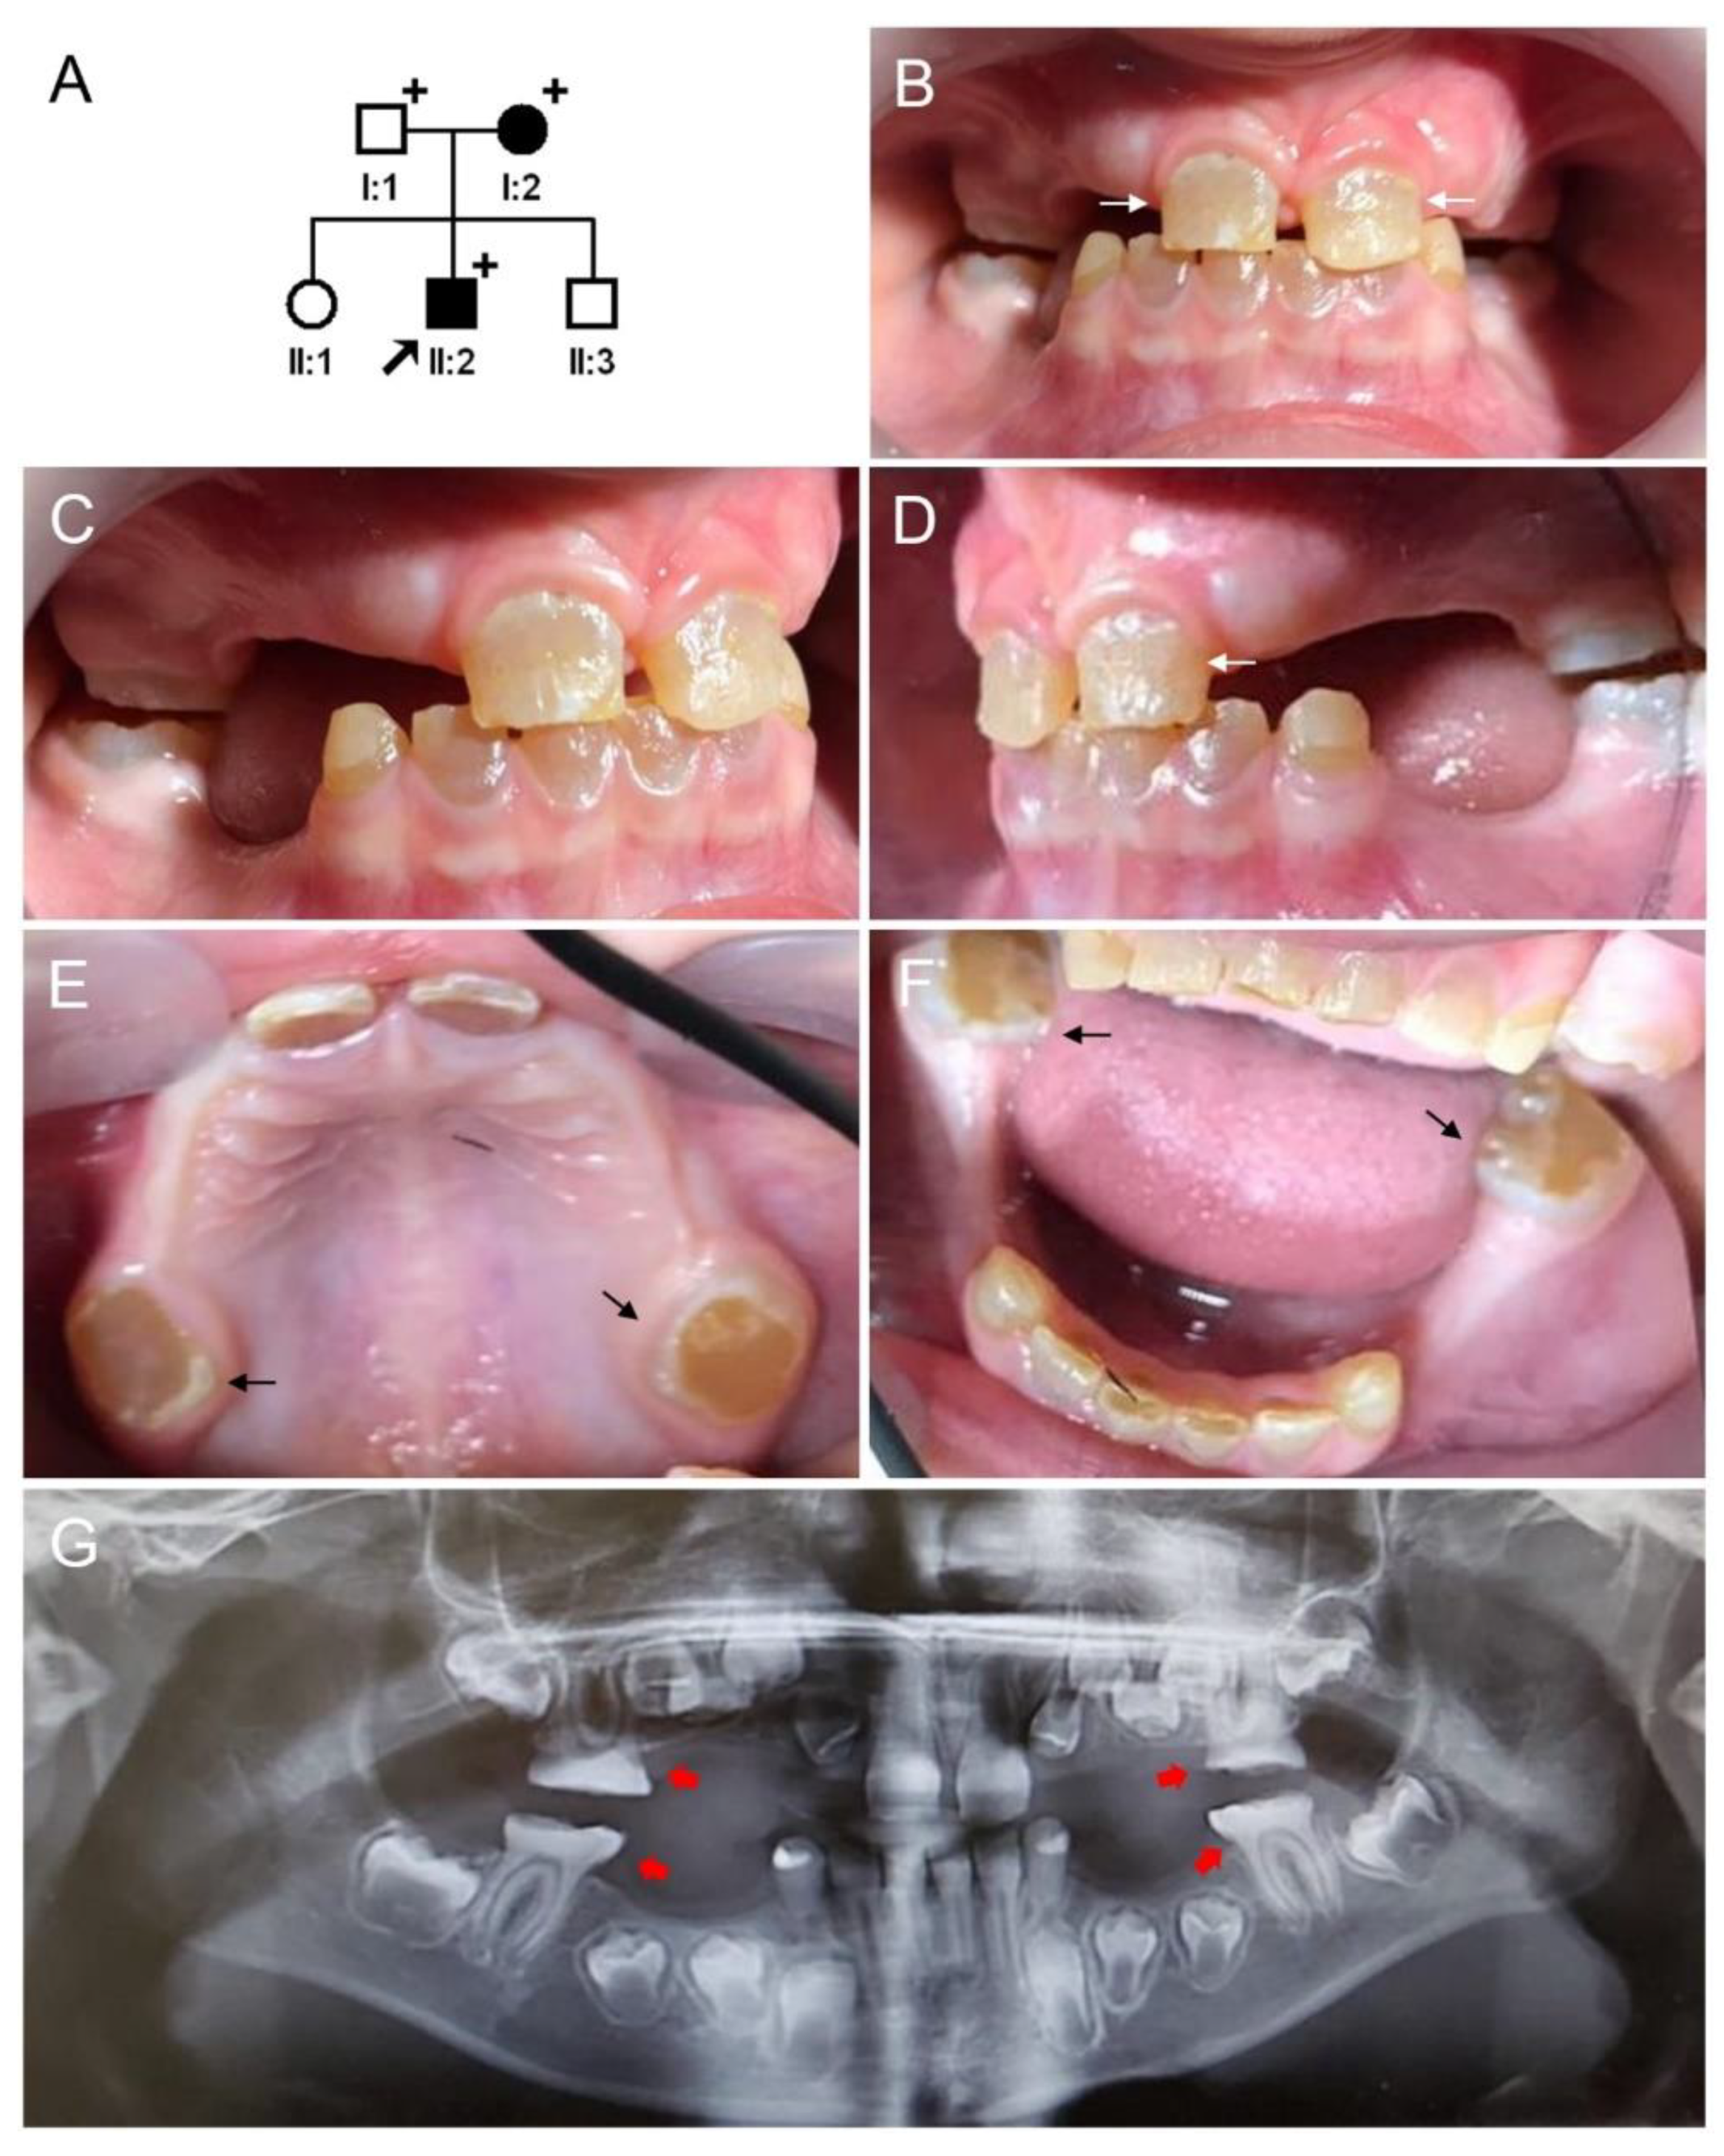

3.1. Clinical Phenotype and Diagnosis of Family 1